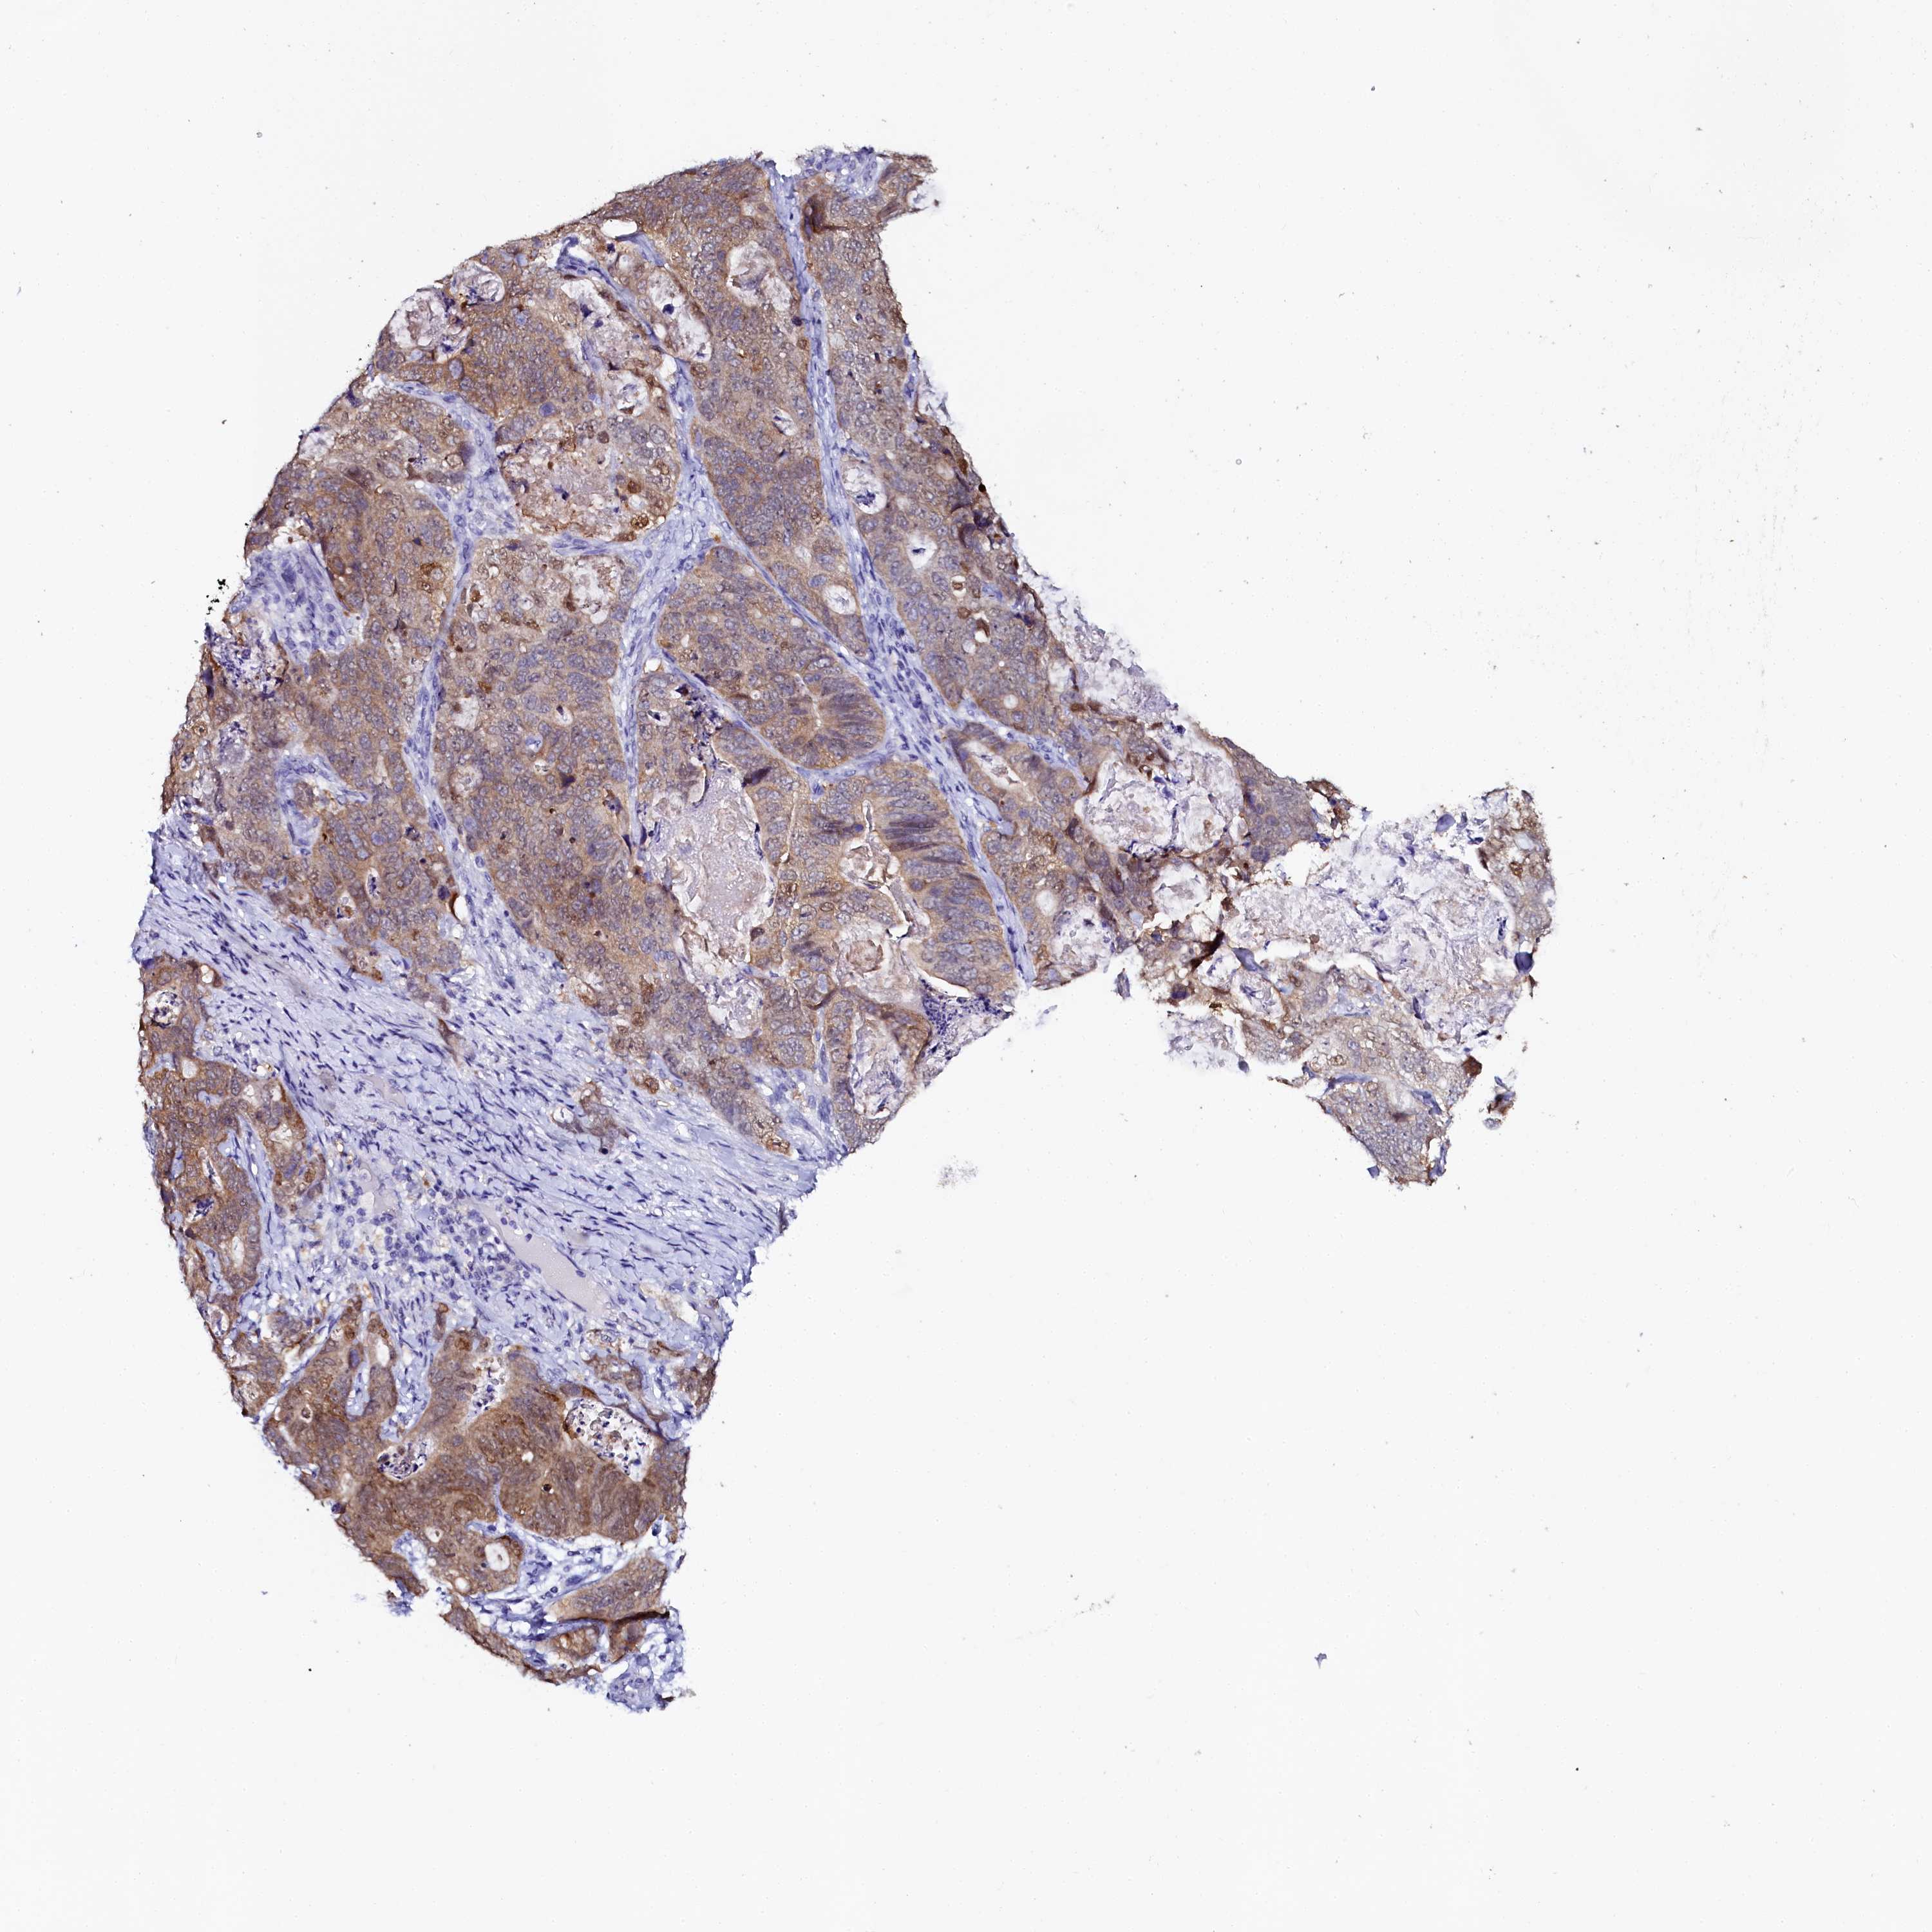

STOMACH CANCER - Protein expressioni

A mouse-over function shows sample information and annotation data. Click on an image to view it in a full screen mode. Samples can be filtered based on level of antibody staining by selecting one or several of the following categories: high, medium, low and not detected. The assay and annotation is described here.

Note that samples used for immunohistochemistry by the Human Protein Atlas do not correspond to samples in the TCGA dataset.

Antibody stainingi

Antibody staining in the annotated cell types in the current human tissue is reported as not detected, low, medium, or high, based on conventional immunohistochemistry profiling in selected tissues. This score is based on the combination of the staining intensity and fraction of stained cells.

Each image is clickable and will lead to virtual microscopy that enables deeper exploration of all samples and also displays staining intensity scores, fraction scores and subcellular localization as well as patient and tissue information for each sample.

Antibody HPA040260

Antibody HPA040621

Staining

High

Medium

Low

Not detected

Intensity

Strong

Moderate

Weak

Negative

Quantity

>75%

75%-25%

<25%

None

Location

Nuclear

Cytoplasmic/membranous

Cytoplasmic/membranous,nuclear

Adenocarcinoma, NOS